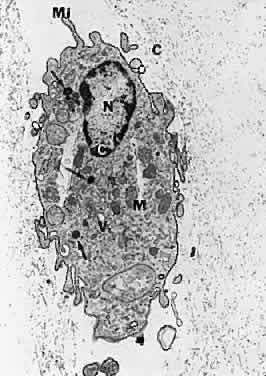

Fig. 20. Ultrastructure of human hyalocyte. A mononuclear cell is seen embedded within the dense collagen fibril (black C) network of the vitreous cortex. There is a lobulated nucleus (N) with a dense marginal chromatin (white C). In the cytoplasm, there are mithochondria (M), dense granules (arrows), vacuoles (V), and microvilli (Mi). (×11,670.) (Courtesy of Joe Craft and Dan Albert, MD)

The phagocytic capacity of hyalocytes derives from the presence of pinocytic vesicles, phagosomes (Fig. 20), and cell membrane receptors that bind immunoglobulin G (IgG) and complement. It is intriguing to consider that hyalocytes are among the first cells to be exposed to any migratory or mitogenic stimuli released during various disease states. Because hyalocytes are essentially tissue macrophages, they may have a role similar to macrophages in other diseases, i.e., to recruit cells and elicit further escalation of the inflammatory response. Whereas in some tissues this may be desirable, in the vitreous this process results in various untoward events, depending on the clinical circumstances. In the case of pars planitis, hyalocytes in the vitreous base may be responsible for antigen processing and eliciting an immune response typical of tissue macrophages that leads to the observed snow banks of inflammatory cells in the peripheral anterior vitreous. Indeed, for these and other reasons, this condition may be more aptly named peripheral anterior vitritis. After failed surgery for rhegmatogenous RD, hyalocytes are likely the first cells to participate in the formation of the contractile membranes that in PVR detach the retina again. The particularly high density of hyalocytes in the vitreous base may be important in the pathogenesis of anterior PVR, wherein the prominence of vitreous fibers also contributes to the disease process by facilitating cell migration and transmitting traction to the peripheral retina, ciliary body, and iris. Thus, the role of these cells must be adequately considered in defining the pathophysiology of PVR, perhaps leading to a new avenue for early intervention.